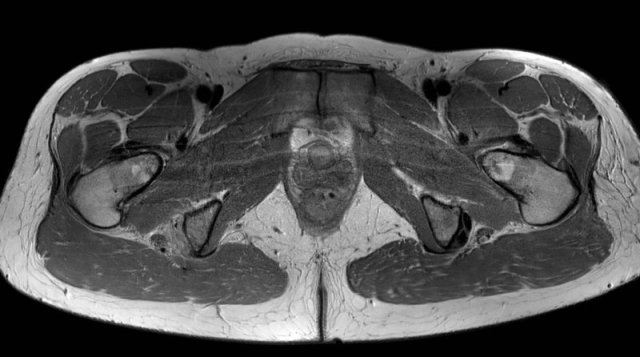

Coronal versus axial

Based on coronal images alone, it is sometimes challenging to exactly classify the amount of distortion. Use the axial images to get a closer look.

On these axial images, high signal and thickening of the left biceps femoris tendon (yellow dotted circle) is seen when compared to the non-injured side (white dotted circle).